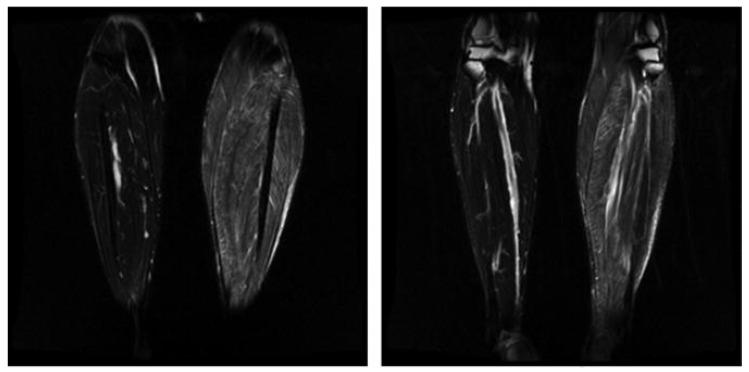

(1) Background: Neurologic and musculoskeletal diseases represent a considerable portion of the underlying etiologies responsible for the widely prevalent symptoms of pain, weakness, numbness, and paresthesia. Because of the subjective and often nonspecific nature of these symptoms, different diagnostic modalities have been explored and utilized. (2) Methods: Literature review. (3) Results: Nerve and muscle biopsy remains the gold standard for diagnosing many of the responsible neurological and musculoskeletal conditions. However, the need for invasive tissue sampling is diminishing as more investigations explore alternative diagnostic modalities. Because of this, it is important to explore the current role of neurosurgical intervention for nerve and muscle biopsies and its current relevance in the diagnostic landscape of neurological and musculoskeletal disorders. With consideration of the role of nerve and muscle biopsy, it is also important to explore innovations and emerging techniques for conducting these procedures. This review explores the indications and emerging techniques for neurological intervention for nerve and muscle biopsies. (4) Conclusions: The role of neurosurgical intervention for nerve and muscle biopsy remains relevant in diagnosing many neurological and musculoskeletal disorders. Biopsy is especially relevant as a supportive point of evidence for diagnosis in atypical cases. Additionally, emerging techniques have been explored to guide diagnostics and biopsy, conduct less invasive biopsies, and reduce risks of worsening neurologic function and other symptoms secondary to biopsy.